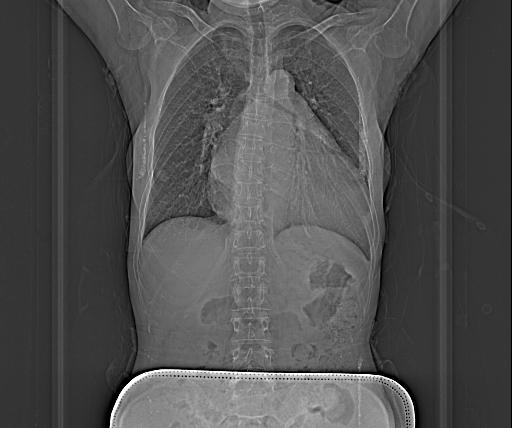

该患者为56岁中年女性,因反复胸闷胸痛、气促10+年,加重1月,2025819日到我院心血管内科住院治疗。入院后完善检查,提示:1.风湿性心脏病:二尖瓣中度狭窄伴重度关闭不全、主动脉瓣重度狭窄伴重度关闭不全、三尖瓣中度关闭不全;2.先天性心脏病:室间隔缺损、右室流出道狭窄;3.左心房及左心室显著扩大(左房舒末前后径:65mm,左房收末前后径54mm,心电图提示心房颤动,血液检验结果提示肝功能及胆红素明显升高,考虑肝淤血。为求进一步治疗,患者于829日转入心脏大血管外科,给予积极抗心衰、营养支持等治疗919心脏大血管外科主任赖应龙带领向军博士、彭泰峦医生等人在手术中心主任涂发平及医护团队配合下成功为患者实施了八种手术,术后患者安全返回心脏大血管外科重症监护室。术毕食道超声提示:二尖瓣仅残留少量关闭不全外,其余所有心脏问题全部解决,心律转为窦性心律。患者于术后2小时苏醒,成功撤离呼吸机,于术后10小时开始进食,目前已下床活动。

心影明显增大

主动脉瓣及瓣环明显钙化